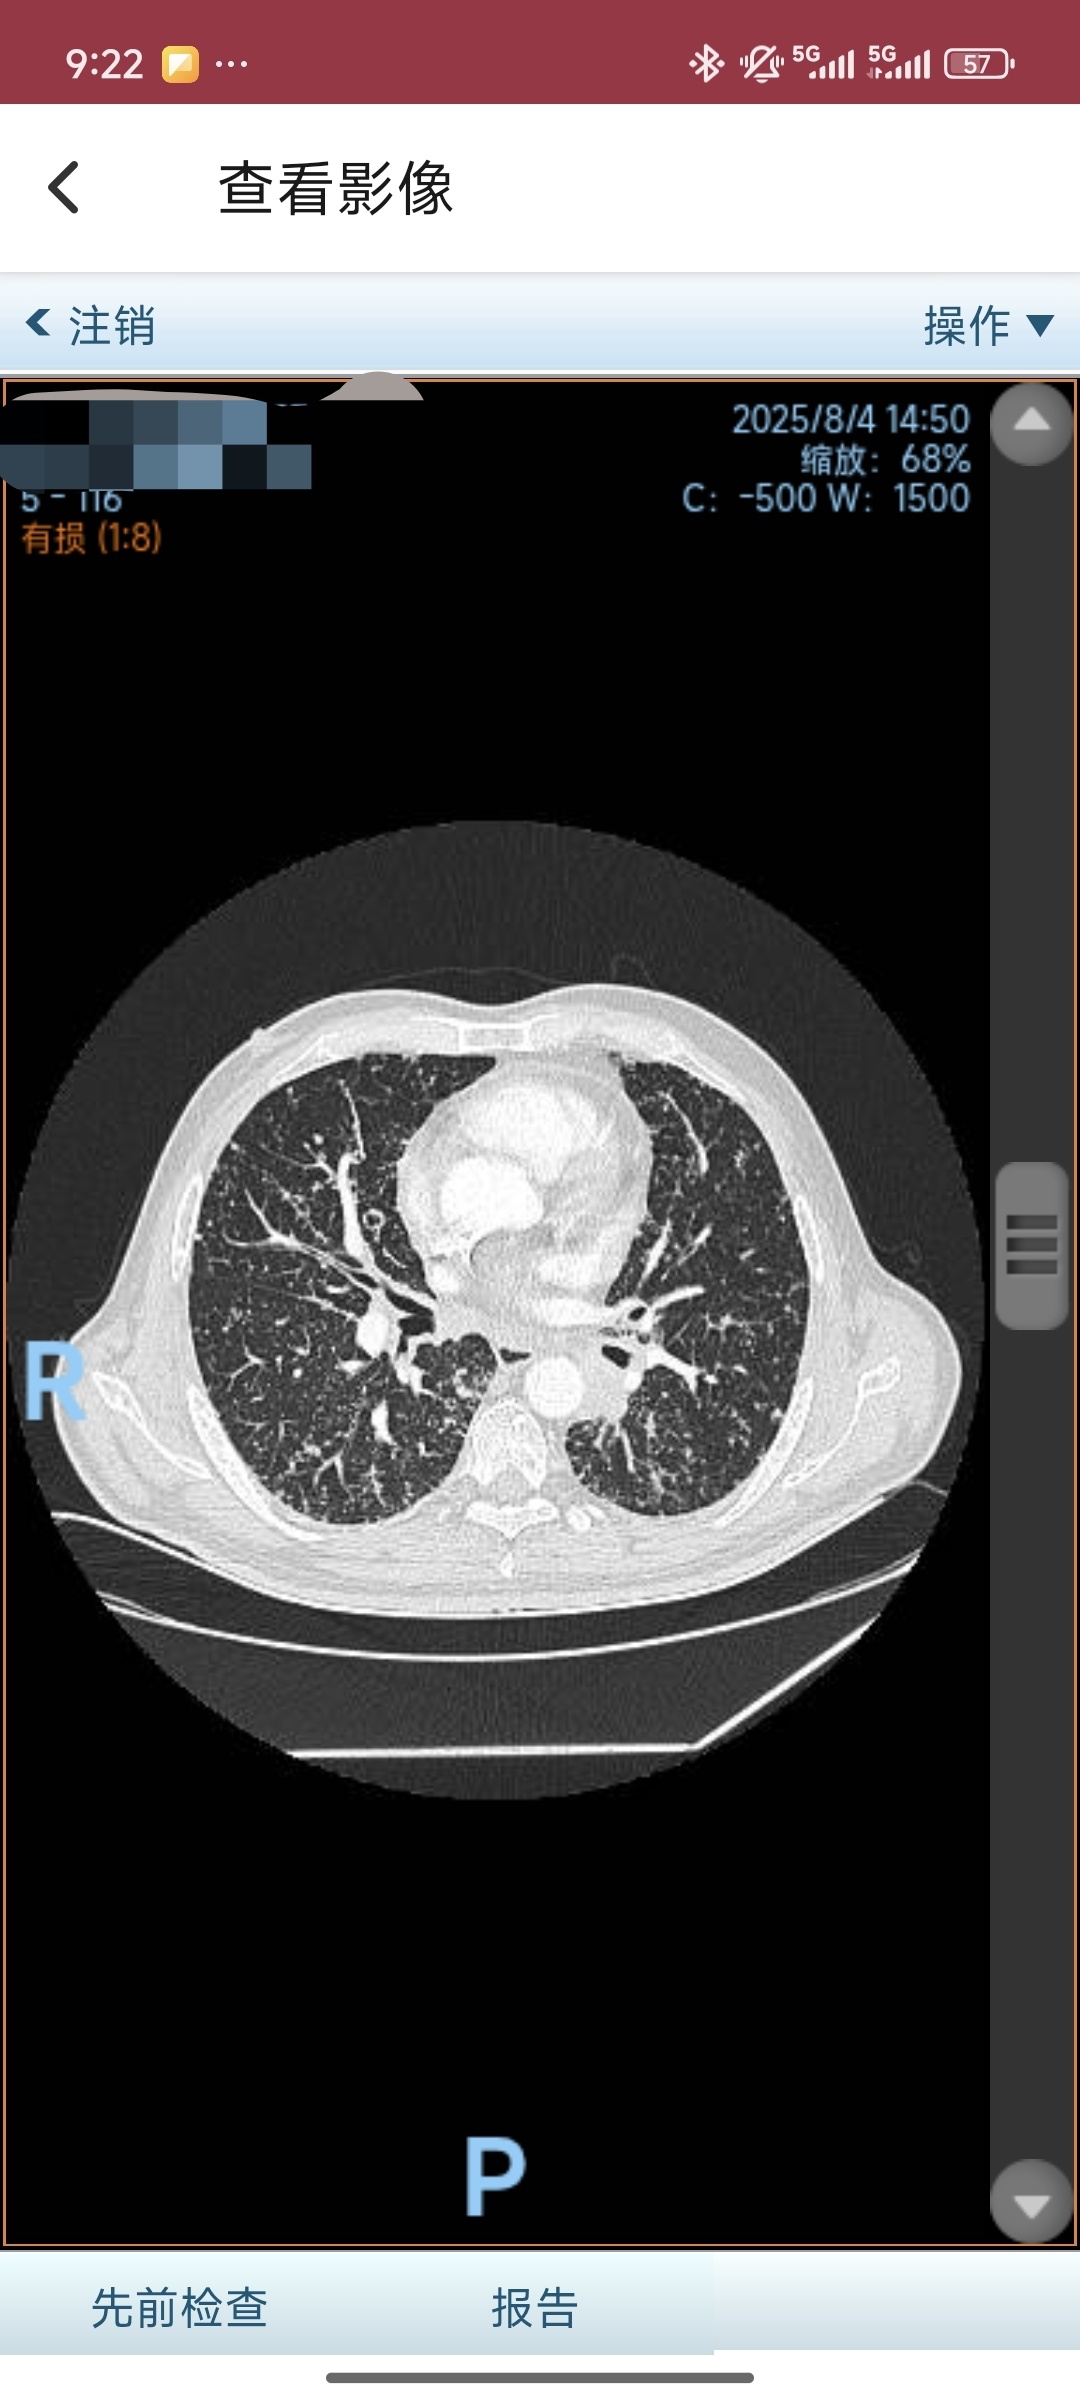

2025-08-04本院复查胸部CT:左下肺癌疗后改变伴远端肺内阻塞性炎性灶,双肺癌性淋巴管炎伴多发转移,部分缩小;纵隔、双肺门、锁

骨上区及胸肌间多发淋巴结缩小,密切追查;左侧极少量胸水同前;少量心包积液同前;多发骨转移同前。